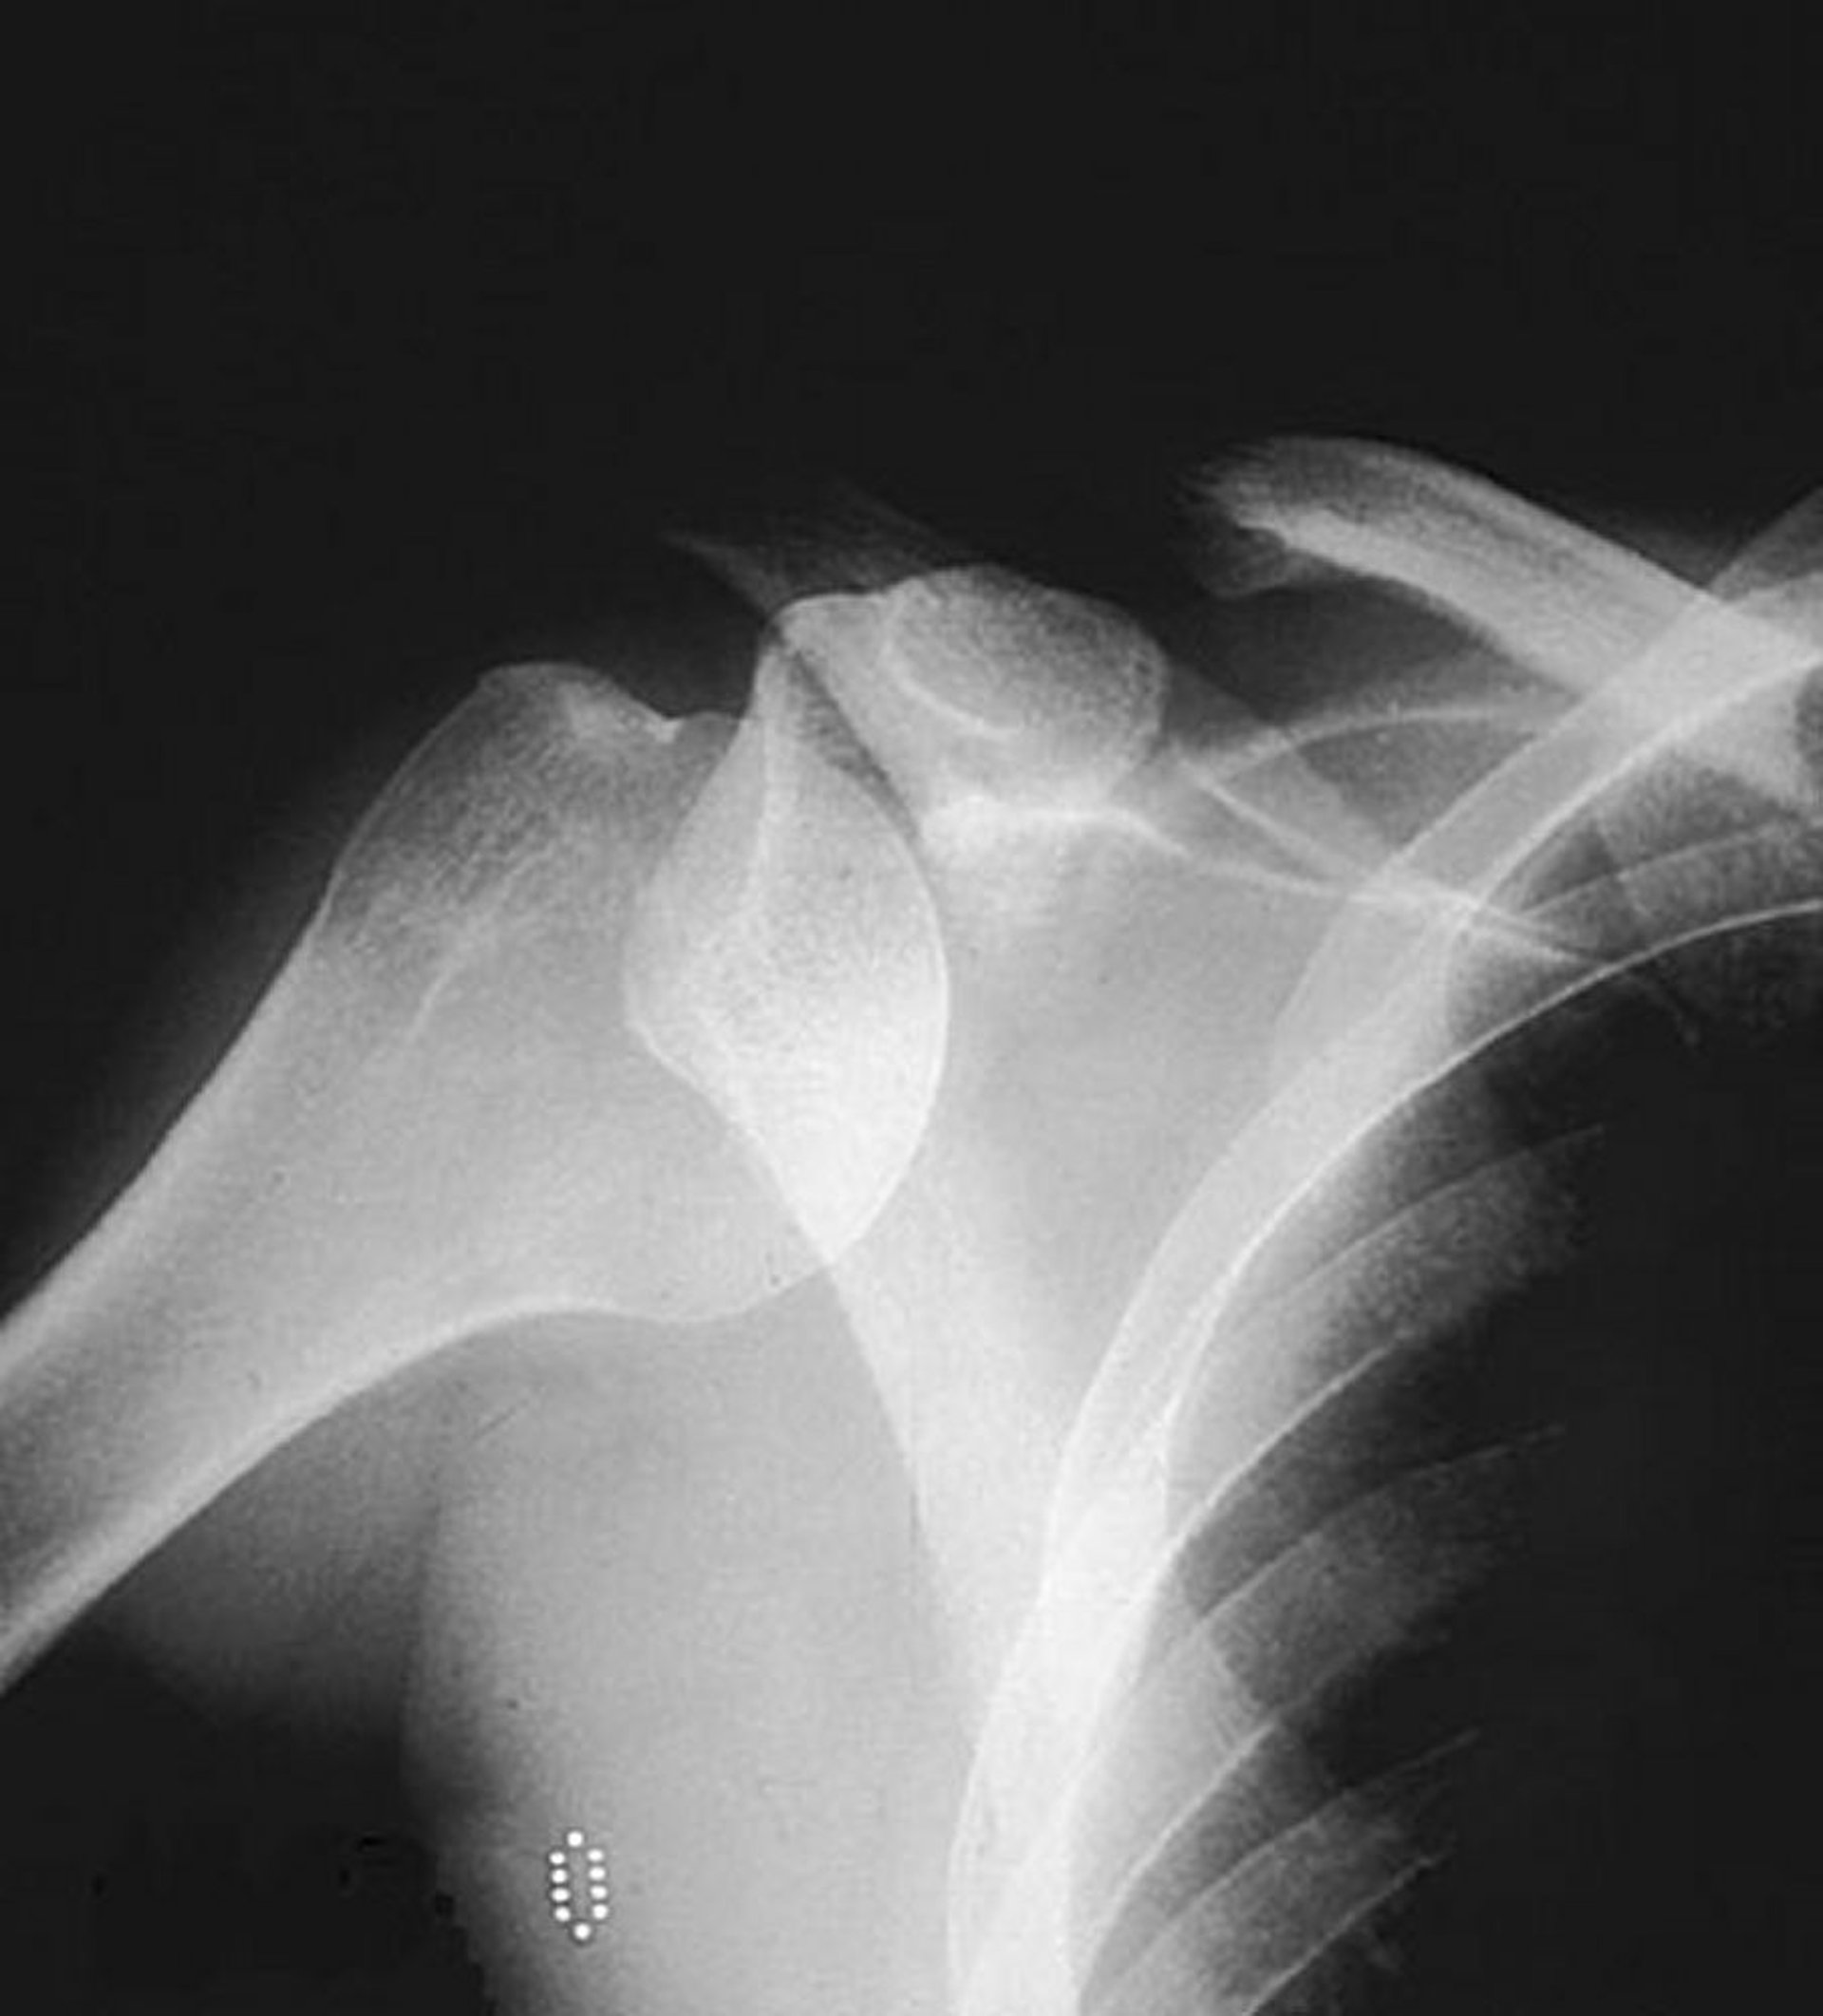

Luxation antérieure glénohumérale (épaule)

Une radiographie simple de face montre la tête humérale hors de son emplacement habituel dans la fosse glénoïde, ce qui suggère une luxation antérieure.